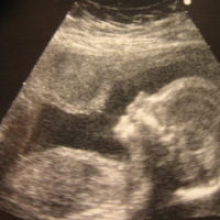

Lichidul amniotic: ce rol are și ce este anormal